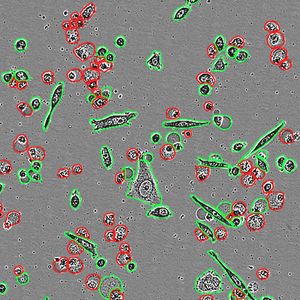

SEP 04, 2023CancerMetastasis is one of the main obstacles in treating cancer. Studying circulating tumor cells (CTCs) and CTC clusters at ...